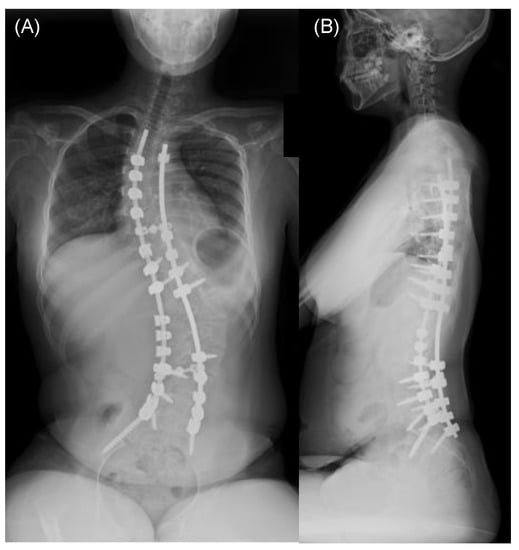

Representative Case Presentation